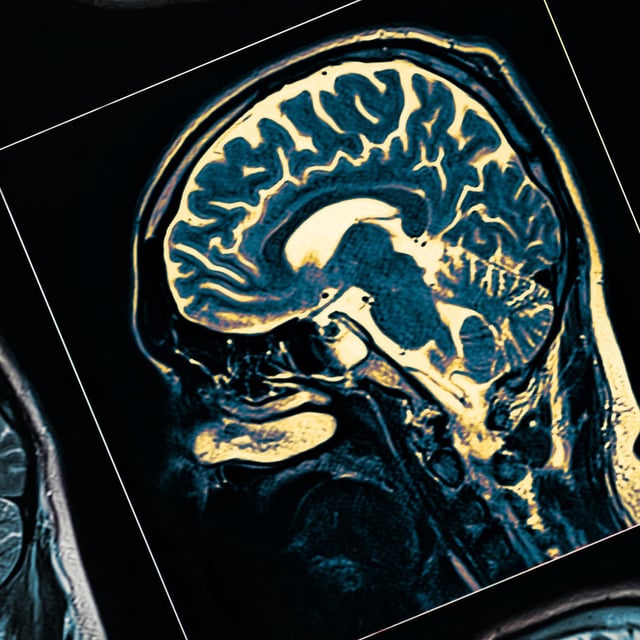

Scientists Directly Visualize Suspected Parkinson’s-Triggering Oligomers in Human Brain Tissue

ASA–PD increases fluorescence signal over background to expose nanoscale alpha‑synuclein clusters in post‑mortem brains.